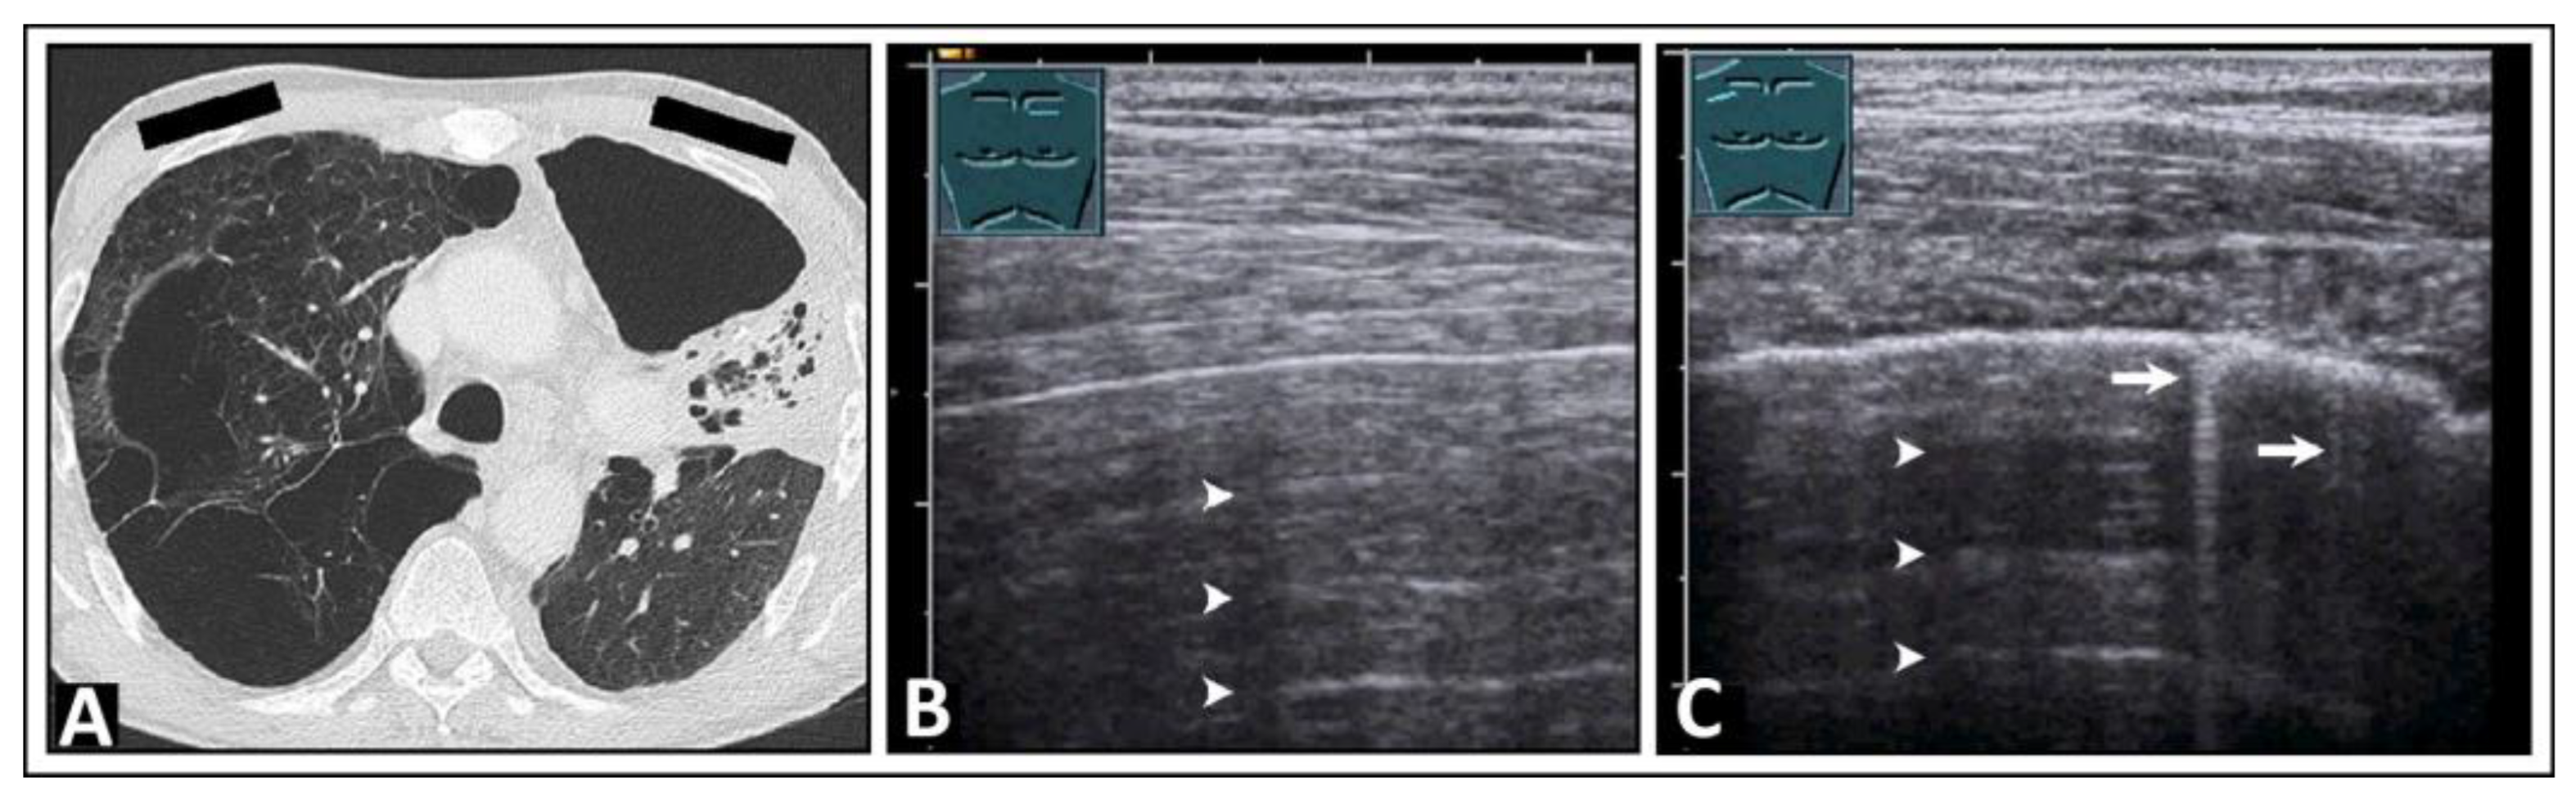

5. Pneumonia

6. Interstitial Lung Disease

7. Other Pathologic Situations

8. Pleural Artifacts with Simultaneous Presence of Consolidation